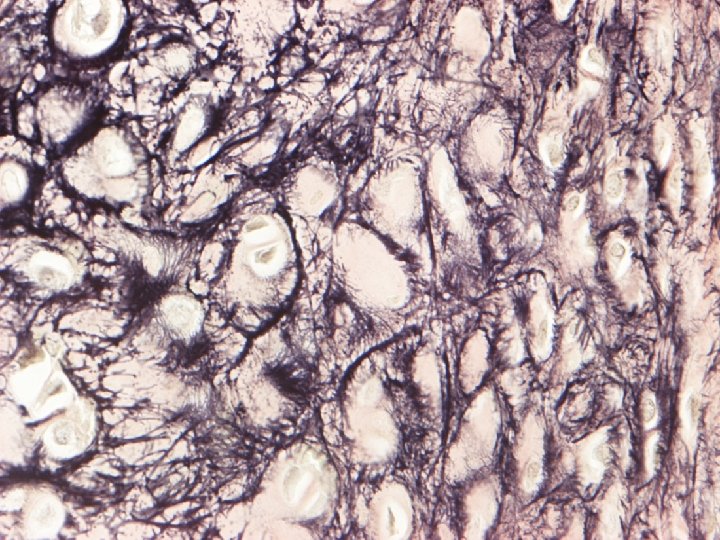

elastic cartilage